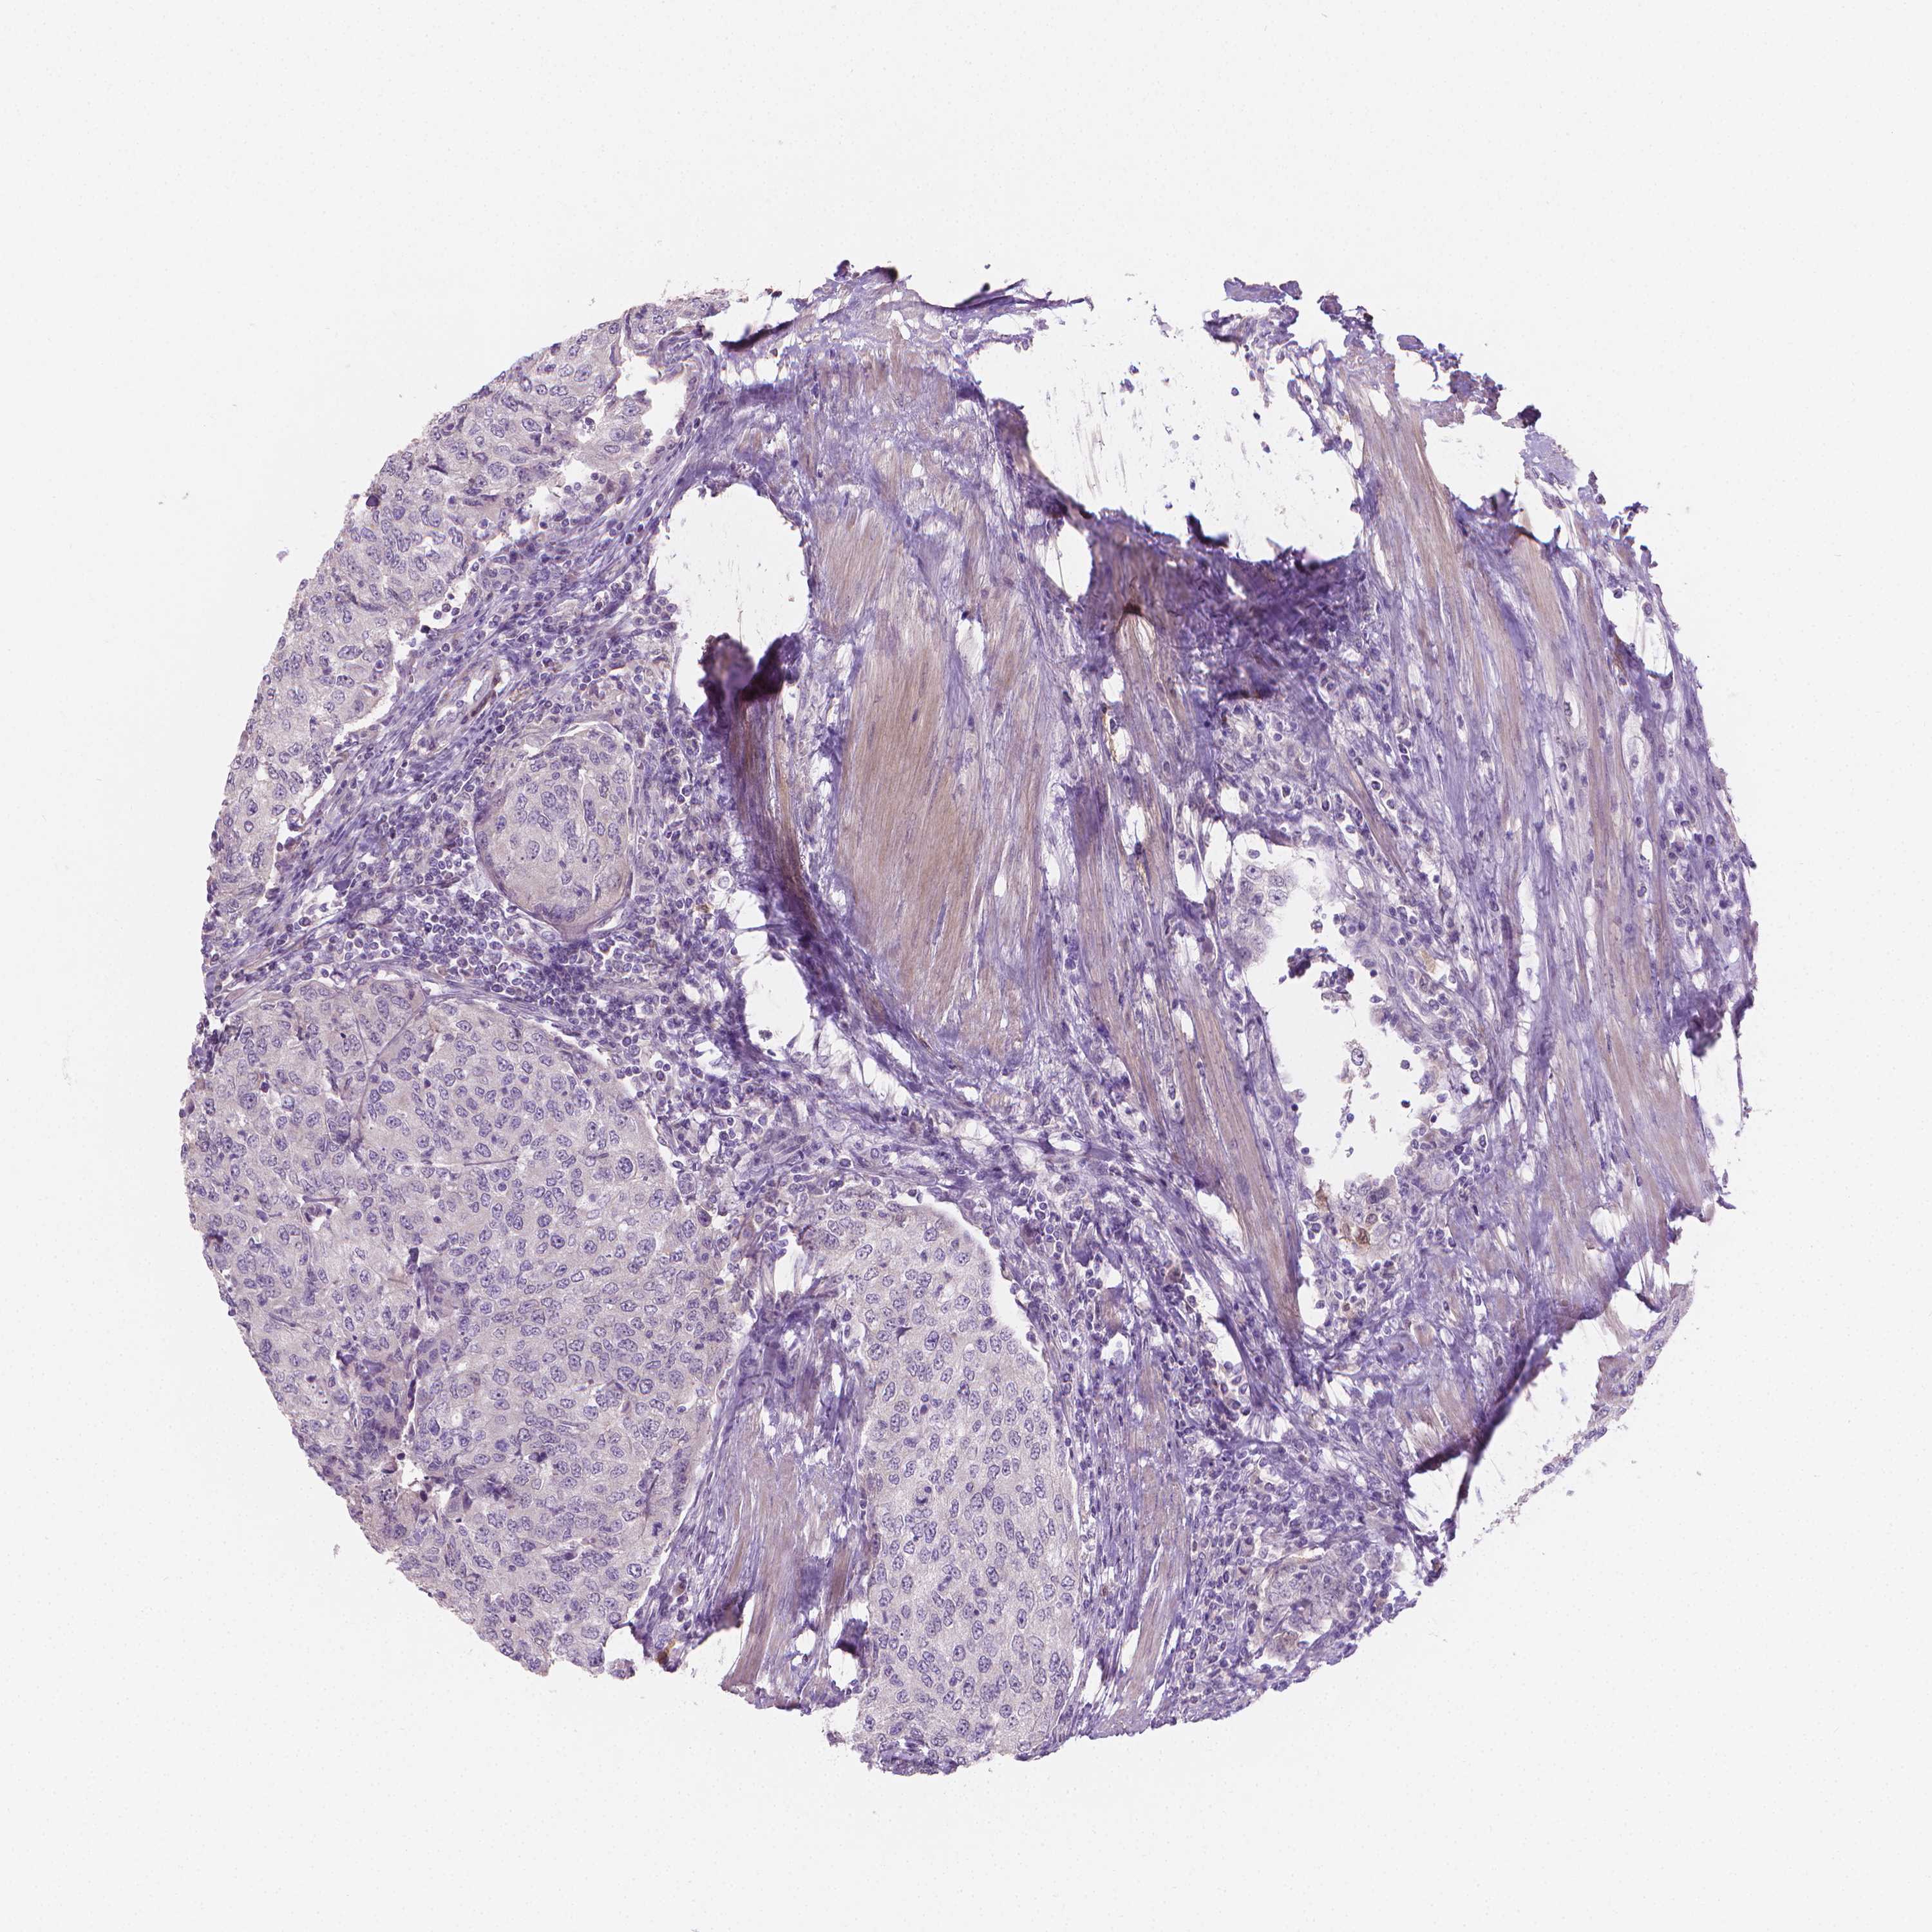

UROTHELIAL CANCER - Protein expressioni

A mouse-over function shows sample information and annotation data. Click on an image to view it in a full screen mode. Samples can be filtered based on level of antibody staining by selecting one or several of the following categories: high, medium, low and not detected. The assay and annotation is described here.

Note that samples used for immunohistochemistry by the Human Protein Atlas do not correspond to samples in the TCGA dataset.

Antibody stainingi

Antibody staining in the annotated cell types in the current human tissue is reported as not detected, low, medium, or high, based on conventional immunohistochemistry profiling in selected tissues. This score is based on the combination of the staining intensity and fraction of stained cells.

Each image is clickable and will lead to virtual microscopy that enables deeper exploration of all samples and also displays staining intensity scores, fraction scores and subcellular localization as well as patient and tissue information for each sample.

Antibody HPA023313

Antibody HPA064826

Staining

High

Medium

Low

Not detected

Intensity

Strong

Moderate

Weak

Negative

Quantity

>75%

75%-25%

<25%

None

Location

Nuclear

Cytoplasmic/membranous

Cytoplasmic/membranous,nuclear

Urothelial carcinoma, High grade

Urothelial carcinoma, NOS

Urothelial carcinoma, Low grade